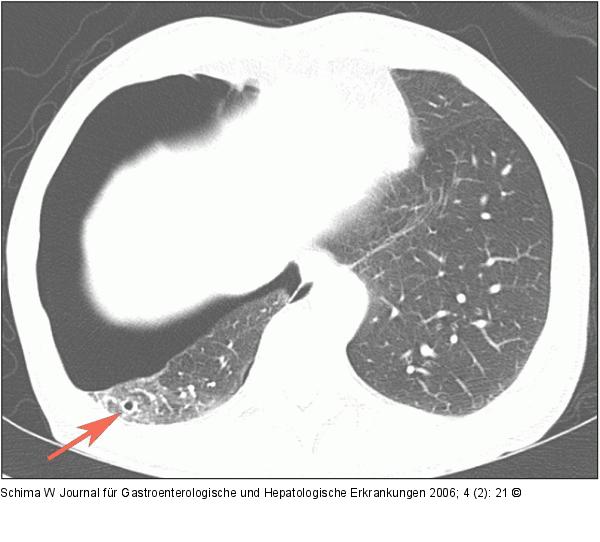

Abbildung 2a: Pneumothorax Das axiale CT-Bild zeigt einen großen Pneumothorax, man erkennt das Loch im Lungenparenchym durch die Magensonde (Pfeil). |

Das axiale CT-Bild zeigt einen großen Pneumothorax, man erkennt das Loch im Lungenparenchym durch die Magensonde (Pfeil). |